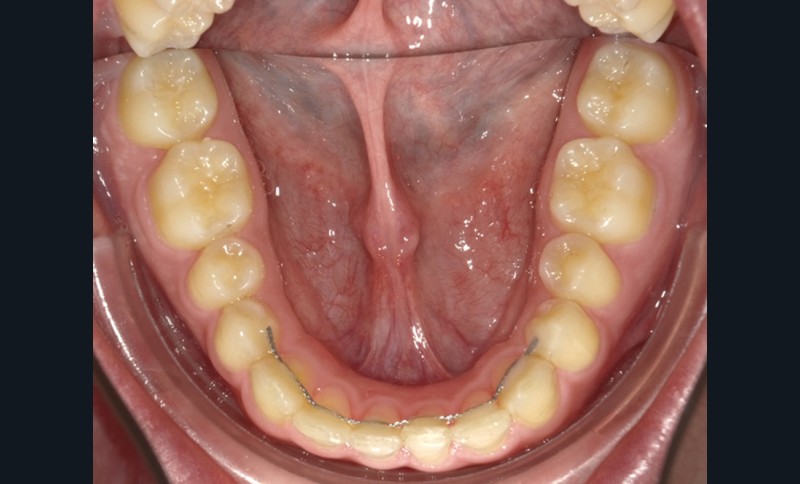

Bien que 23 % des patients reconsultent dans les dix années qui suivent la dépose de leur appareil [5], la contention est longtemps restée le parent pauvre des nouvelles technologies. Ceci est en train de changer et le Dr Serge Dahan nous éclairera sur l’apport des outils numériques, dans la réalisation des contentions de nouvelle génération. Ces dernières peuvent être fixes ou amovibles.

Dans le premier cas, il s’agit de plaques de nickel-titane usinées (fig. 10a-b) ou de fils de contention, pliés par un robot. Dans le deuxième cas, il s’agit de gouttières thermoformées sur des modèles (fig. 11), modifiés ou non, voire bientôt des gouttières imprimées directement.